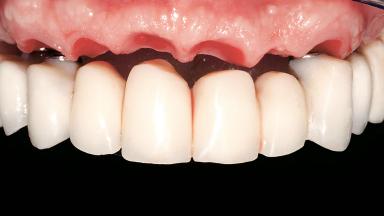

Immediate Loading of Six Implants in the Maxilla and Final Restoration with a Full-Arch CAD/CAM Zirconia FDP

A 63-year-old male patient was referred for a consultation and treatment of partial edentulism in the maxilla. The patient presented with residual anterior teeth and declined a partial removable prosthesis. He reported that the maxillary posterior teeth had been extracted due to mobility and periodontal disease two months before the consultation. The patient’s chief complaint was that his residual maxillary teeth were mobile and that he was unable to chew. The patient’s desire was a stable and comfortable fixed maxillary rehabilitation. The patient was a light smoker (fewer than 10 cigarettes/ day), and his medical history was without significant findings. He was not on any regular medication at the time of consultation. The extraoral examination revealed a normal physiognomy with a correct distribution of the facial thirds. The patient presented a low lip line, and the transition line between teeth and soft tissues was not exposed during a forced smile.